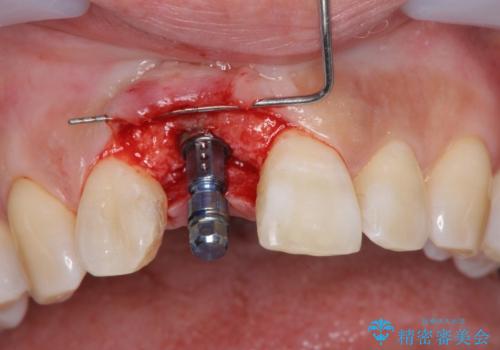

審美的・機能的に良好な位置に埋入するには、骨量が十分ではなかったため骨の造成を併用したインプラント埋入外科手術を行います。

前歯のインプラントを審美的に仕上げるには、インプラント周囲に十分な骨の量と厚みのある歯肉、そして埋入位置の精密な位置付けが重要です。